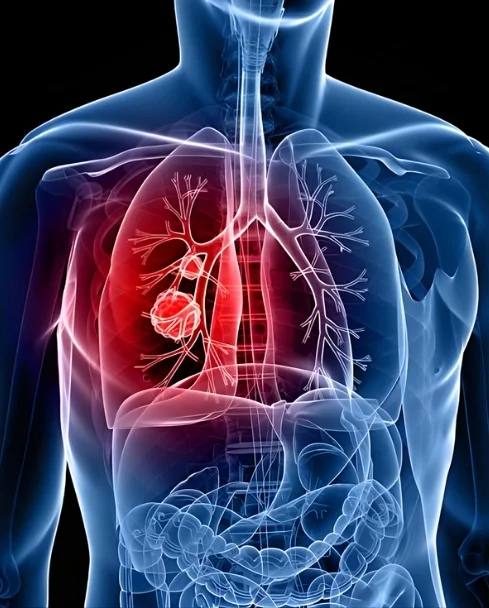

What is Thoracic Cancer?

Thoracic cancer is a type of cancer that develops in the chest area, including the lungs, esophagus (food pipe), and the lining around the lungs. It can affect breathing, swallowing, and overall health if not treated on time. Lung cancer is the most common form of thoracic cancer and requires timely medical attention for better outcomes.

These cancers may develop due to factors like smoking, air pollution, or other health conditions. Common symptoms include a persistent cough, chest pain, shortness of breath, and unexplained weight loss. Early diagnosis and the right treatment approach can help manage thoracic cancer effectively and improve quality of life.